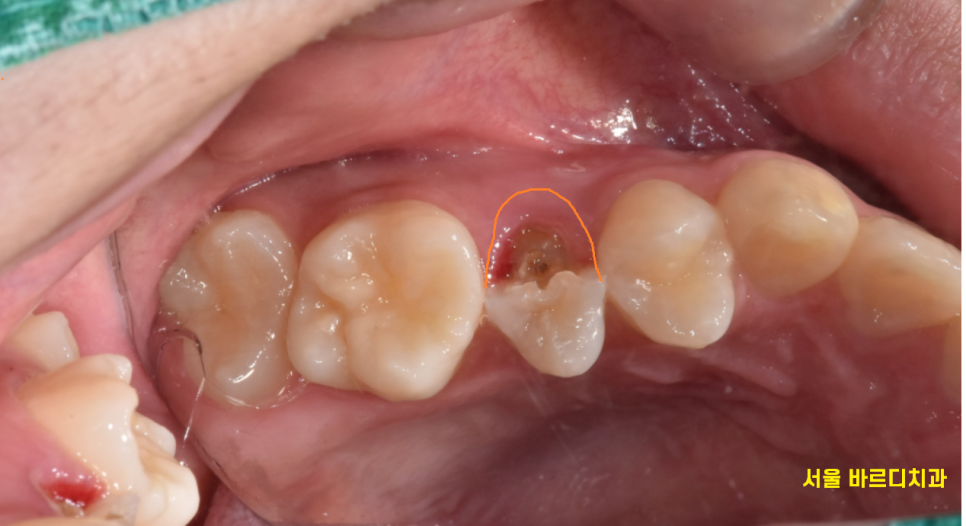

치아가 뿌리쪽까지 부러지긴 했지만

절반 정도가 남아 있어서

신경치료 후 살려보기로 하였습니다.

한쪽 부분이 잇몸에 박힐 정도로

많이 부러져서

잇몸도 절제하고

보철물 제작을 시행하였는데요.

작은 어금니라 힘을 많이 받지 않는 부위라

살려 볼 수 있었습니다.